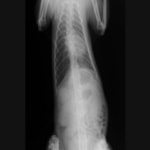

術前のレントゲン

■ 症例:10歳 ドーベルマン 主訴:突然の嘔吐、虚脱